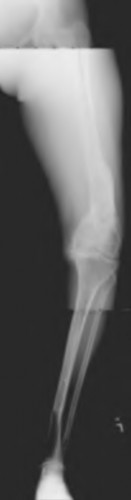

A 78-year-old female sustains a periprosthetic femur fracture 10 years after a cemented THA. Radiographs show a fracture around the tip of the stem with a loose femoral component and poor proximal bone stock, but adequate diaphyseal bone.

What is the most appropriate surgical treatment?

Explanation